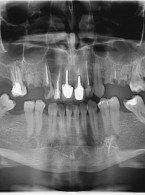

Rehabilitacja protetyczna z zastosowaniem leczenia implantologicznego (...)

Zobacz więcej

12.50PLN